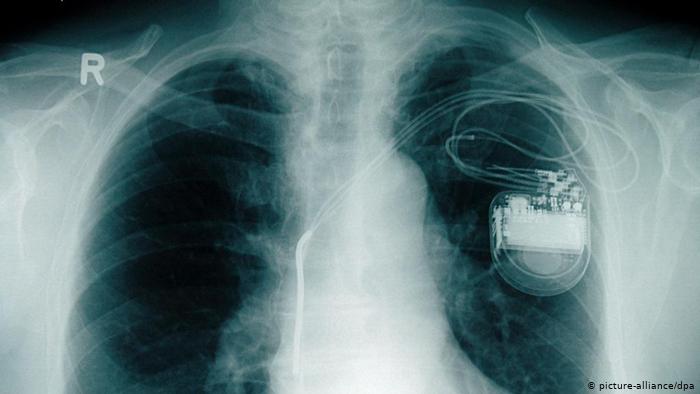

جهاز مولد نبضات القلب

وإذا كان نبض القلب بطيئا جدا، يستعان عند هذه الحالة المرضية بجهاز طبي يزرع في جسم الإنسان يقوم بتوليد نبضات الكترونية ترسل إلى عضلة القلب. هذا الجهاز الطبي تم استعماله لأول مرة في عام 1958 والنوعيات الحديثة منه تستطيع العمل في جسم الإنسان لمدة تتراوح بين خمسة أعوام واثني عشر عاماً.